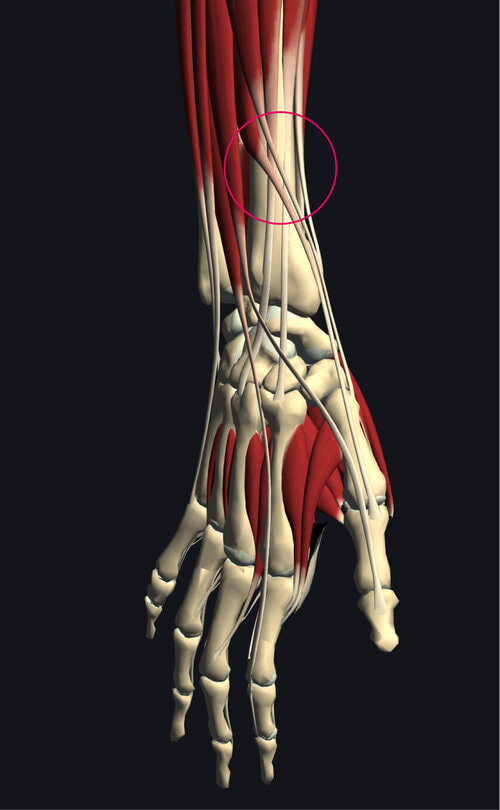

結果は「交差点症候群(インターセクションシンドローム)」

きっと一般の方は聞いたこともないことと存じます。

手首の背側、親指よりのところには、

親指の動きに関係する長母指外転筋・短拇指伸筋、

手首の動きに関係する短橈側手根伸筋・長橈側手根伸筋という、

intersection.jpg

筋肉が交差する部分があり、手指や手首を酷使することにより、

炎症を起こし、痛みと腫れを出現させ"ギシギシ"音を発生させます。